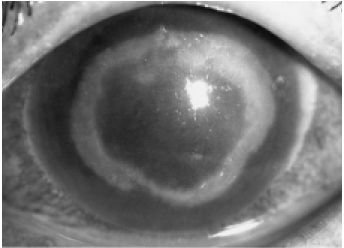

アカントアメーバ角膜炎(重症)

眼の痛みが強いのが特徴で、涙もたくさん出ます。また、白眼の充血も非常に強くなります。

初期の視力低下は軽度ですが、徐々に見えにくくなり、進行すると重度の視力障害になります。

目やには軽度で、通常 片眼のみに起こる片眼性に疾患です。